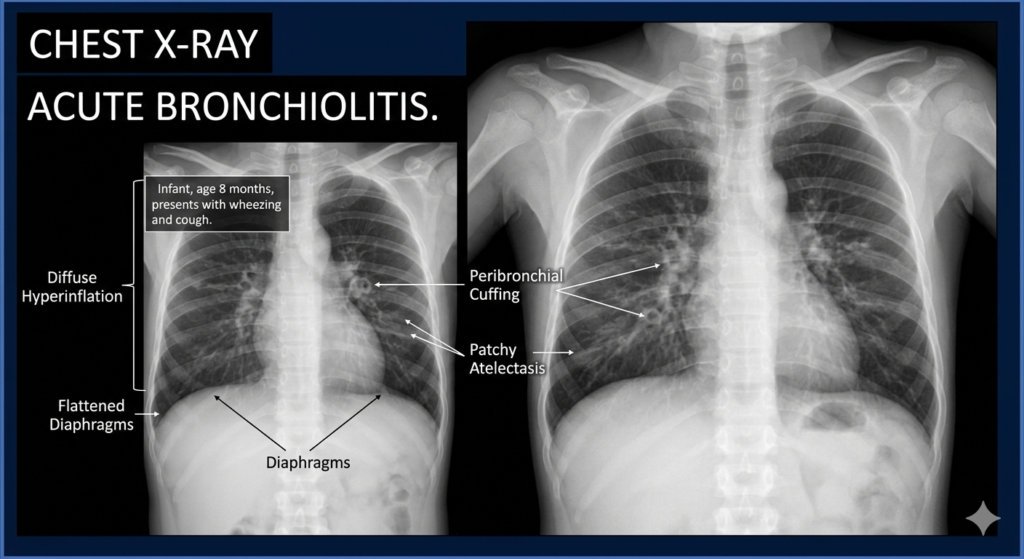

Blood tests and CXR are not routinely indicated. CXR changes may be misleading, as they can mimic pneumonia and may lead to unnecessary use of antibiotics.

Possible CXR changes include :

- Hyperinflation (most common)

- Segmental collapse/consolidation

- Lobar collapse/consolidation.